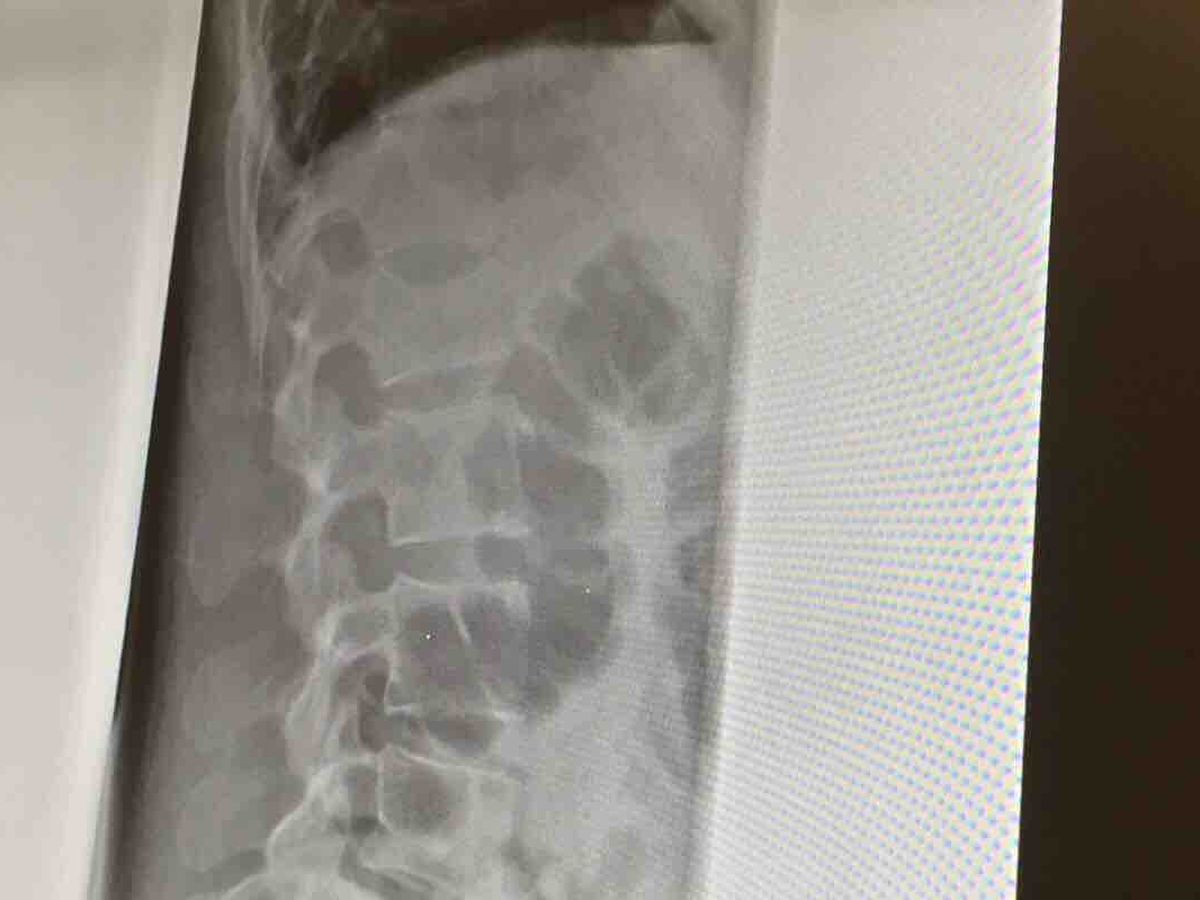

I got hit by a car while riding my bike to work on Monday. I missed all this week and am not allowed to return to work until the end of next week. The picture is my fractured L1 vertebra. It’s the worst pain I’ve ever felt in my life and without insurense  I could really use your help and generosity so I can pay for medical bills while I working on taking legal action. Any little bit helps. Thank you so much for reading.